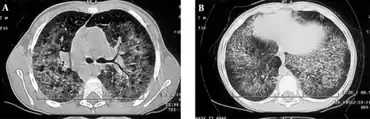

| Diagnostic method | MRI, Chest radiography[1] |

- Chest radiography